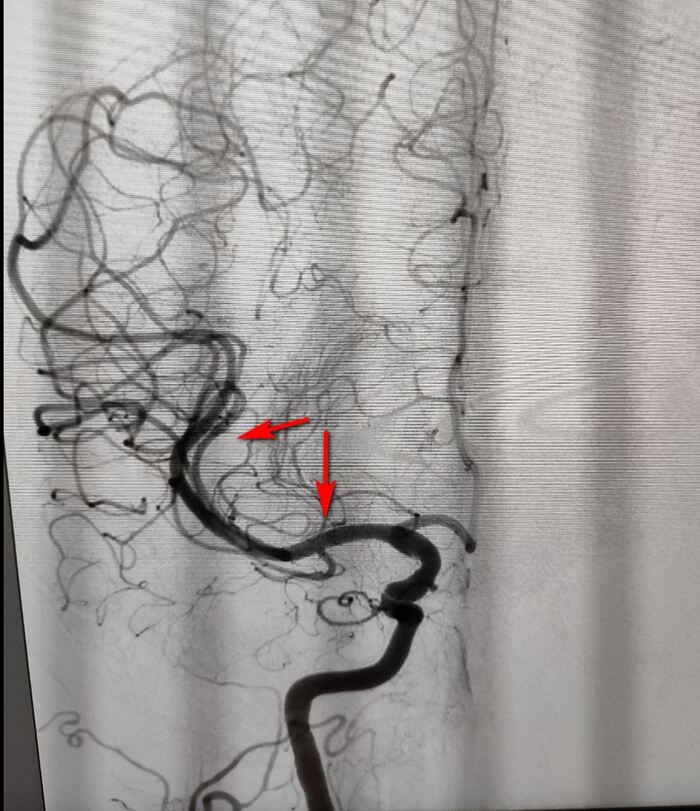

Кстати, повторное исследование на КТ г/м на следующий день показало - гиподенсивную зону в левом полушарии. что окончательно подтвердило диагноз: "Ишемического инсульта в бассейне ЛСМА".